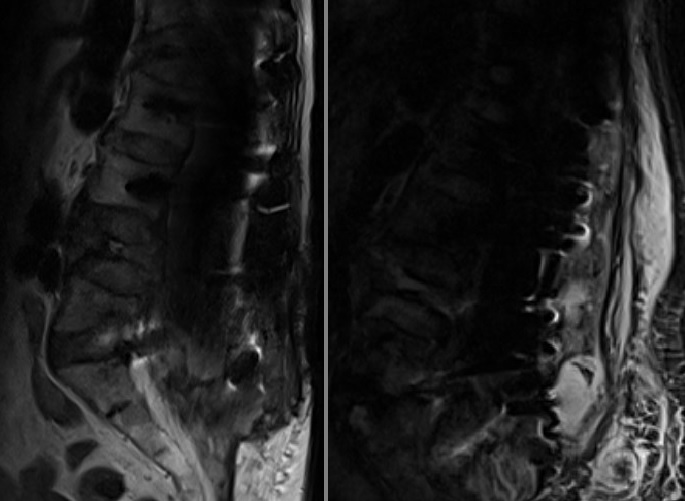

L4 vertebra kırığı BT

Resim 2: Bilgisayarlı tomografide L4 vertebrasındaki yükseklik kaybının bir ay önceki direkt grafiye kıyasla belirgin arttığı, bu seviyede kanalı daralatan bir kemik fragman bulunduğu, eski L1 kırığı nedeniyle konulan sementli vidanın en alt vidalarında (L3) hafif gevşeme bulguları olmakla beraber sistemin işlevsel olduğu görülüyor.

L4 vertebra kırığı MRG

Resim 3: MRG incelemesinde L4 vertebrasında akut/subakut kırıkla uyumlu görüntü izleniyor.